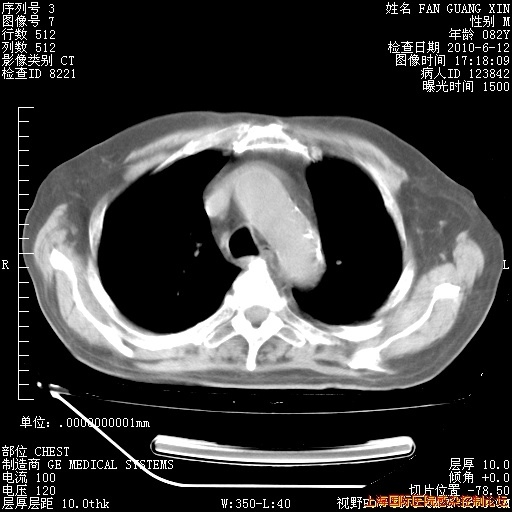

6月12日肺窗

6月12日纵膈窗